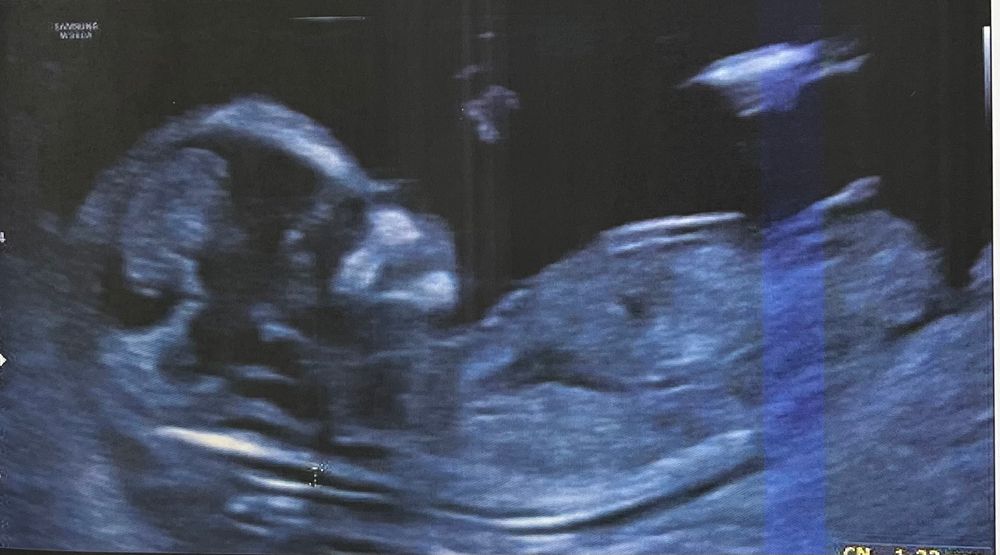

13 недель и половой бугорок

Девочка, я б сказала, что и губы уже сформированы, если я верно вижу

Похоже на девочку, бугорок параллелен позвоночнику.

Девочка 🤩♥️ половой бугорок параллелен позвоночнику

Похоже на УЗИ моего первого ребёнка , дочка